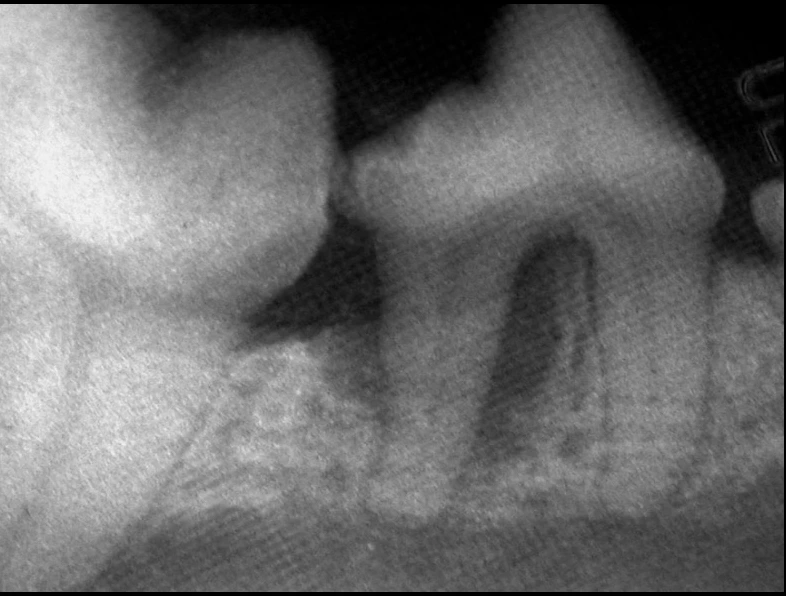

(These photos are of the same tooth)

These pictures are all the same tooth!

The 2nd picture shows the dental xray. The tooth is clearly abscessed. We can’t take dental xrays unless the pet is anesthetized because the digital dental sensor (the part of the machine that goes in the pet’s mouth) has a 9 thousand dollar replacement cost! We don’t stick it into a mouth unless the pet is anesthetized.